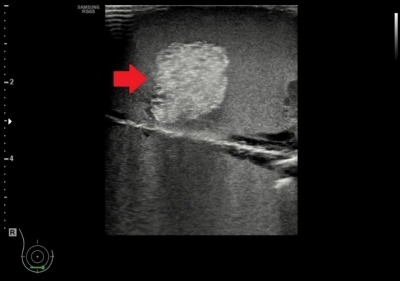

• ให้ภาพอัลตราซาวด์ที่เห็นก้อนเนื้อชนิดต่าง ๆ ชัดเจน

• ให้ภาพอัลตราซาวด์ของเข็มเจาะชัดเจน